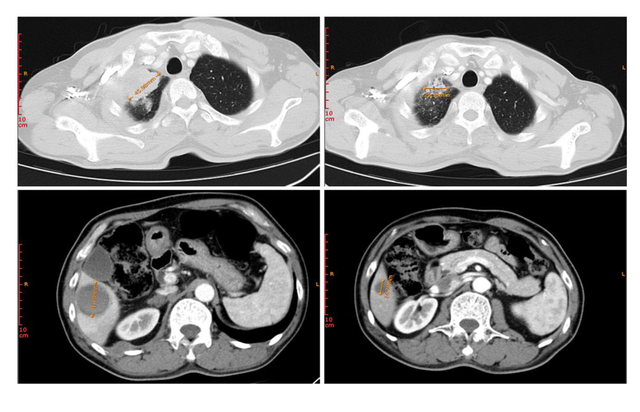

患者1是一名晚期原发性支气管肺癌,在治疗前发现右肺上叶病变以及肝转移,在MRG003治疗后靶病灶总和缩小了超过一半(51.1%)。

患者2为右肺腺癌患者,治疗前右门病变与右胸壁转移性肿瘤大小将近30mm,MRG003治疗后右门病变从29.78mm缩小至15.19mm,而右侧胸壁转移瘤已经几乎看不见。